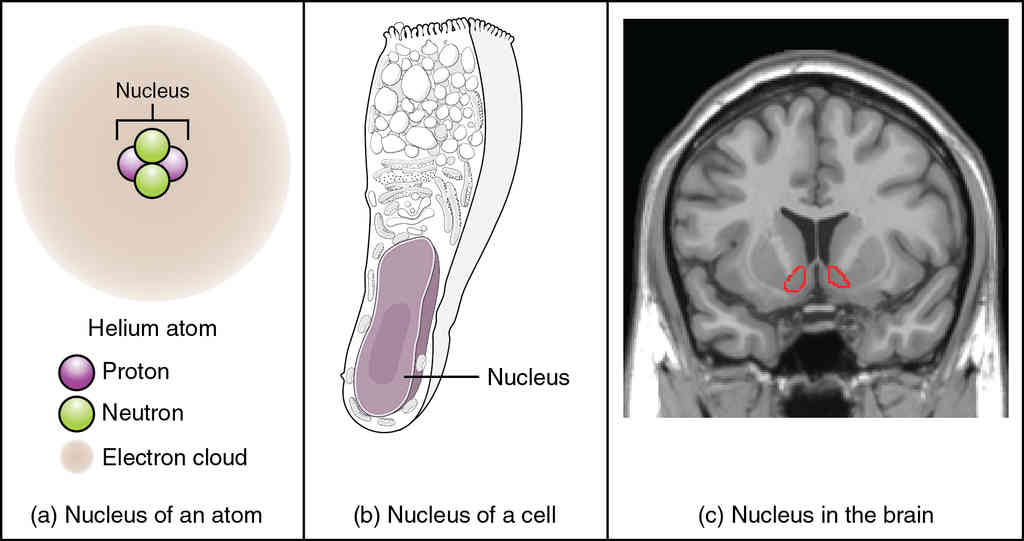

This page is under construction. For now, it is just a resource of the images found in the OpenStax Anatomy and Physiology Handbook. It wil slowly change into a revision tool. Each slide has a number. Use this to refer to the slide. When completed, it will have an unlabelled section, with labelled slides in parallel. On the unlabelled slides, write your answer and use the labelled slide to assess yourself. Keep track by also noting the number on each slide. Improvement at each attempt is important, more so than full marks on a first attempt.